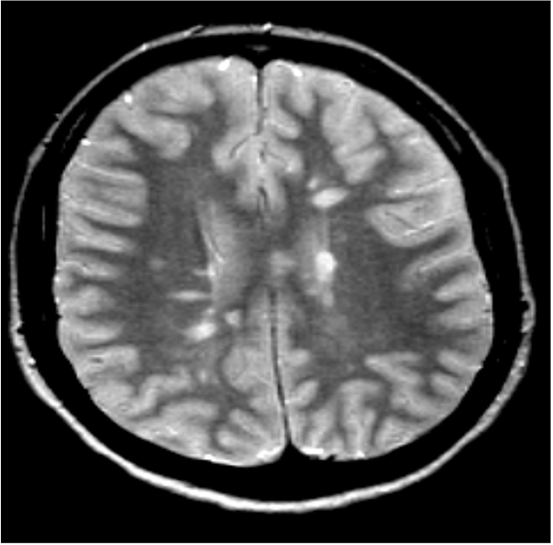

• MRI:

• This is particularly useful in detecting clinically silent lesions.

• More than 90% of patients with clinically definite MS have abnormal MRI.

• Brain MRI

Brain MRI